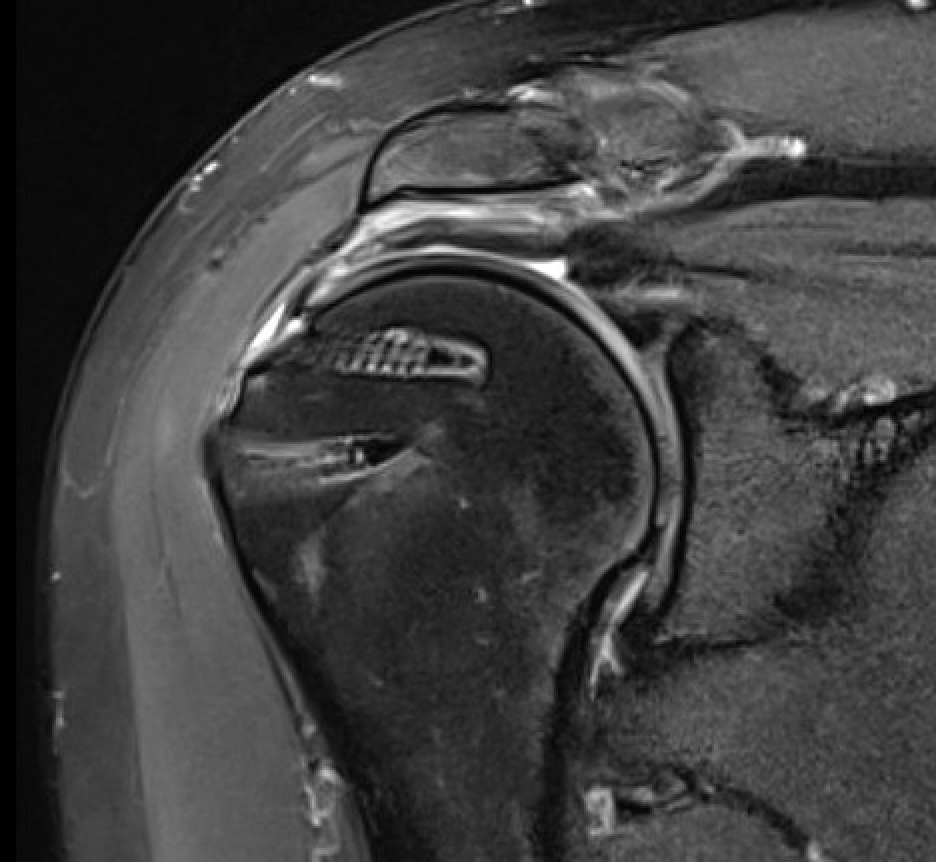

Double row anchors

- medial anchor row at articular margin and tie through medial cuff

- lateral anchor row at lateral footprint used to secure sutures

- increase surface area of cuff repaired to foot print

Trans-osseous equivalent / suture bridge

- cross sutures from medial row to lateral row

- increase contact between cuff and footprint

Medial row anchors

- inserted through additional stab incision for suture management

- just medial to articular cartilage